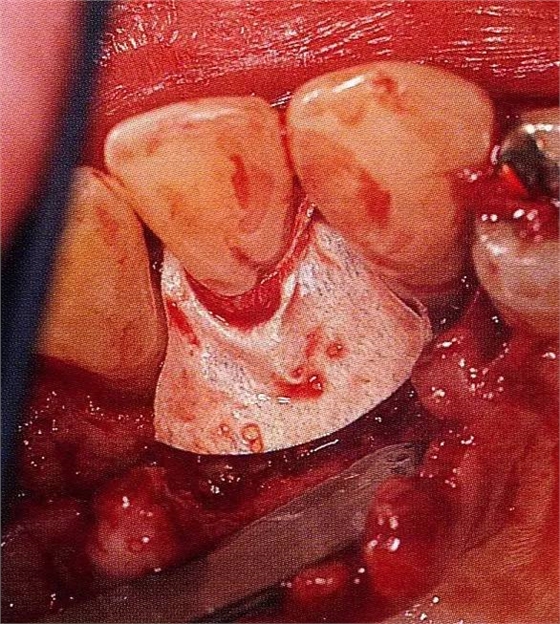

▲圖7-3將posterior interproximal類型的非吸收性覆膜修整后進(jìn)行垂直懸吊縫合做固定。垂直懸吊縫合后,確定覆膜是否會(huì)動(dòng)搖,再將齦瓣與之緊密縫合。